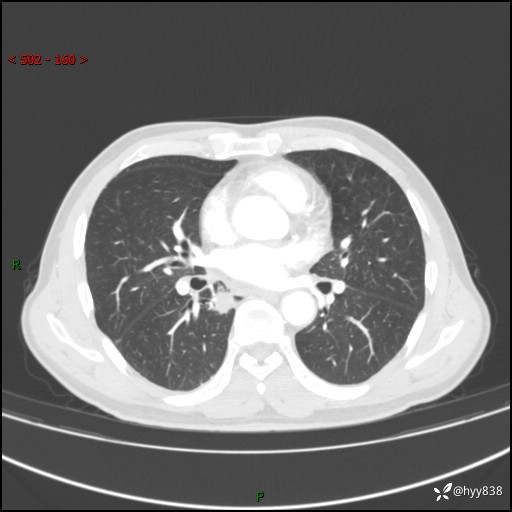

69岁/男,发现肺部病变6天。该有的征象都有,肉芽肿 VS 肿瘤,一念之间---(有结果)

主诉:发现肺部病变6天。

现病史:患者6天前于我院泌尿外科住院,住院期间行胸部CT检查,提示“肺部病变”,患者无畏寒、发热、盗汗、咳嗽、咳痰、咯血、胸痛、呼吸困难,无反酸、腹痛、腹泻、头痛、头晕等不适。未予特殊处理,现为进一步诊治,门诊以“肺肿物”收入我科。 患者本次起病以来,精神食欲尚可,大小便正常,体力及体重无明显变化。

胸部CT平扫+增强